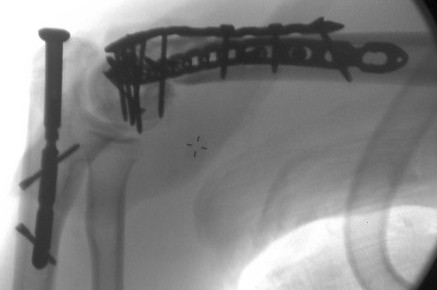

The attached picture is an x-ray of his arm post-surgery.

The ambulance rushed him to a hospital in Gibson City, which is where I went to go see him. The doctor there x-rayed his arm and said that is was broken in many different places. The doctor said that the bones were shattered and he was not confident enough to perform the surgery needed for it, and transferred Matt to the hospital in Urbana. They tried to get his pain under control until the doctor came and looked at his arm in the morning. That morning, another surgeon turned down performing the surgery because the damage was so extensive.

Matt was attacked on a Saturday night at around 10pm and it wasn't until Monday, around 8am that they found a surgeon who was willing to go in there and try to fix it. During surgery, the surgeon who took on the job, discovered that it was even worse when he got inside than the x-rays even let on. Another bone in the arm had to be broken to fix some of the other broken/fractured bones. Matt was told he will never be able to play guitar again, which is Matt's absolute passion in life. He's been playing for over 15 years and was currently working on several collaborative projects with other musicians to produce potential albums. He's been told that he should get about 30% range of usage of his left arm and hand back, if he gets started on his physical therapy as soon as possible.